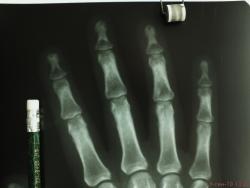

Сотрудница того же травм.пункта) лет 50. сразу извиняюсь за качество снимков. беспокоят боли в суставах кистей. меня заинтересовала структура кости в области ногтевых фаланг- уплотнение структуры, ногтевые фаланги смотрятся плотными. подобные изменения видел часто, но не в такой степени выраженности. может кто знает природу этого уплотнения и когда это встречается. и вообще - норма или нет. заранее благодарен.

это возрастные изменения в Рейнберге подробное описание,- я по поводу склероза; ну и кистовидная перестройка её как признак доа